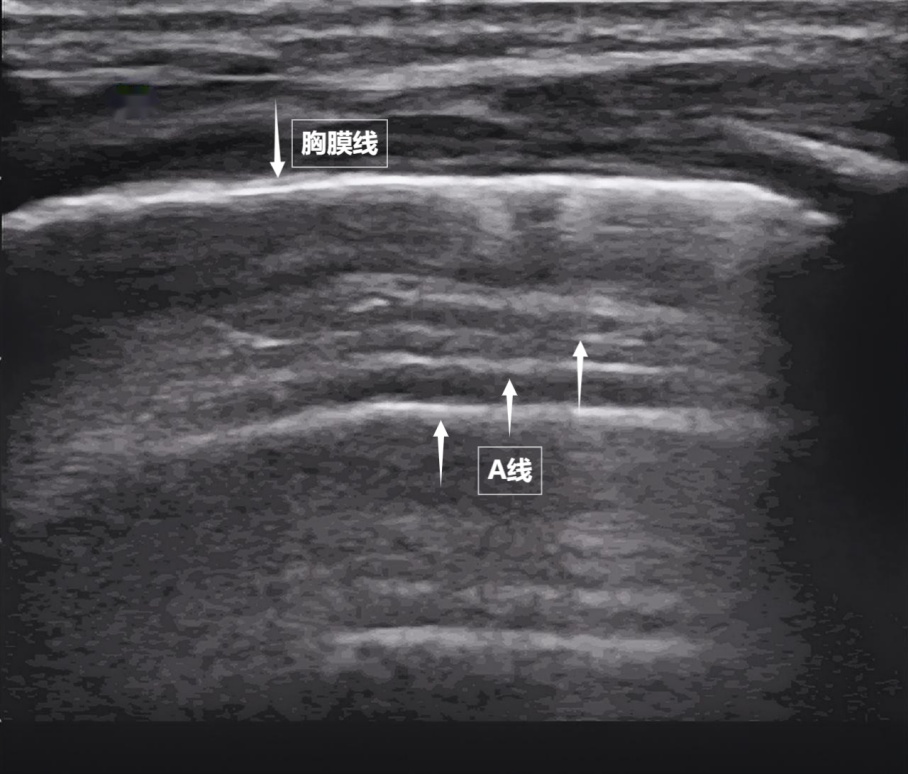

第一景:“海岸线与海浪”——胸膜线与A线

当声波穿过胸壁肋骨缝隙,首先会遇到紧贴肺表面的光滑薄膜——壁层胸膜和脏层胸膜。两者紧密相贴,中间没有多余的气体或液体。它们在屏幕上呈现为一条明亮、光滑的水平线,共同构成了胸膜线。这条线就是肺的“海岸线”。在它的下方,由于肺泡内大量气体对声波的强烈反射,会出现一系列与胸膜线平行的、等间距的、重复出现的明亮平行线,像海浪般不断向屏幕深处延伸,这就是A线(见下图)。A线是正常含气肺部的典型标志。它的存在直接提示肺表面含气充足,胸膜腔内无异常积液或气体。

图为正常新生儿肺部超声表现